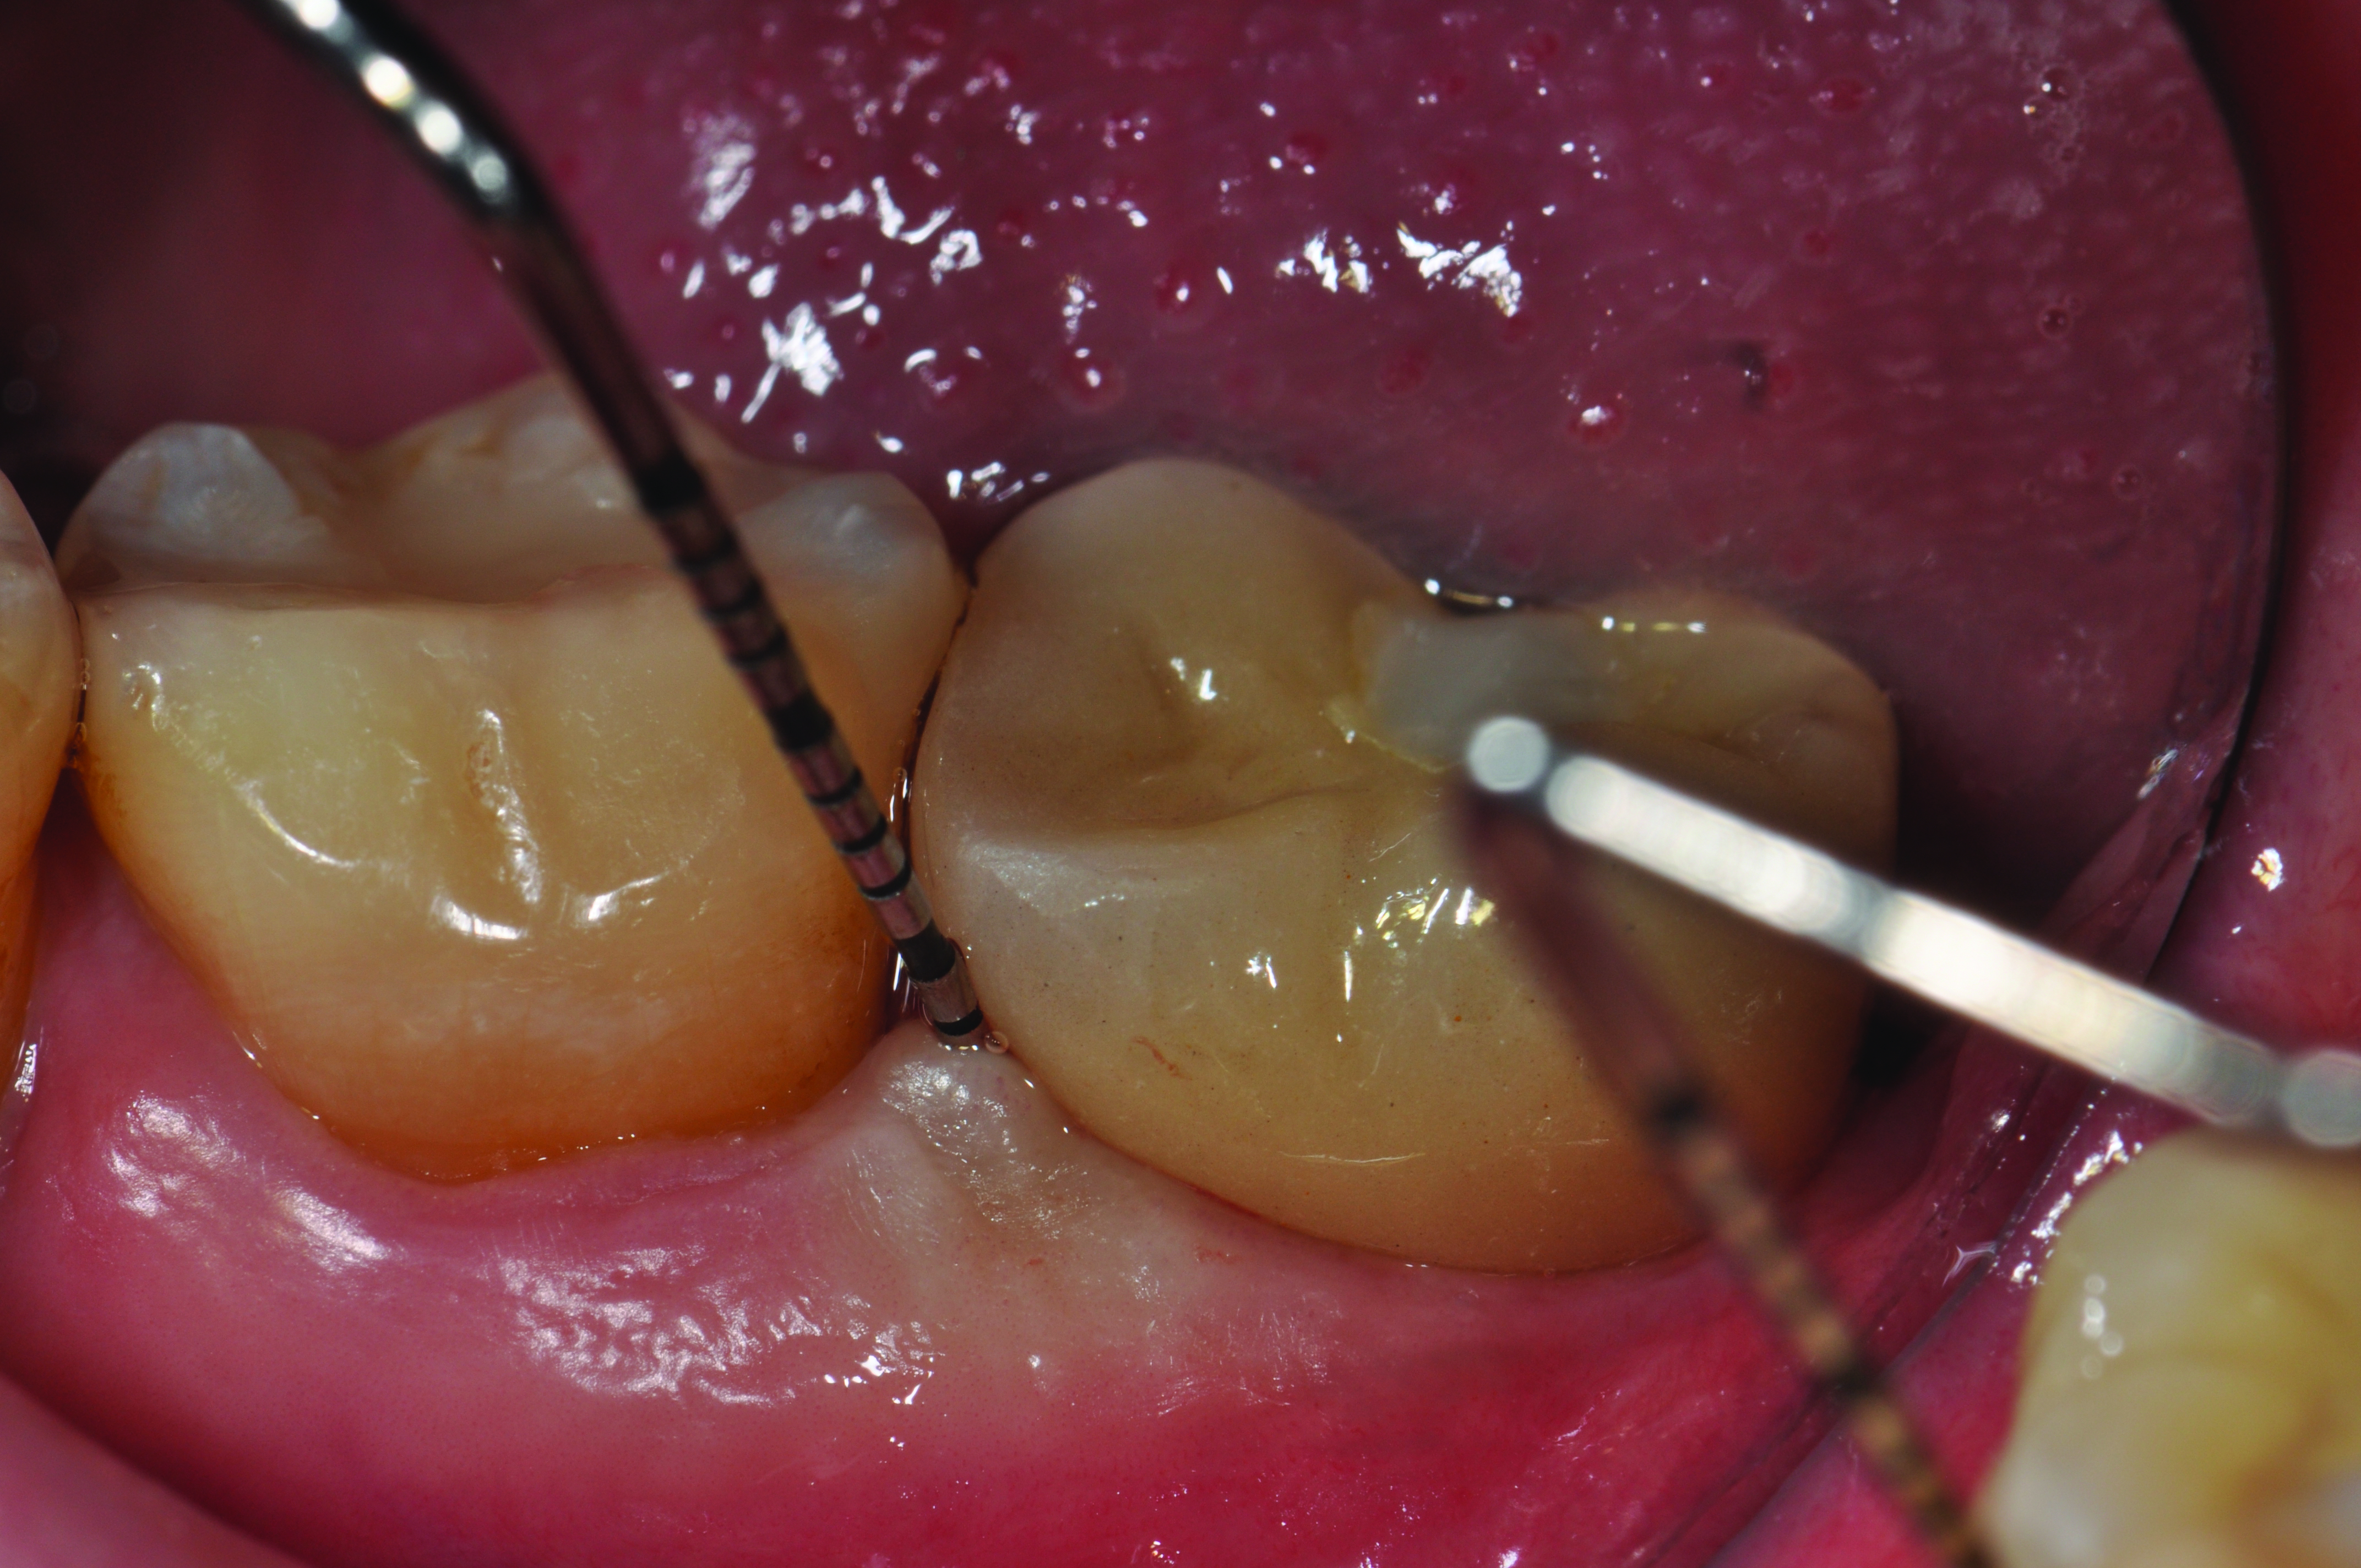

Clinical view of a maxillary left second premolar in an 73-year-old patient with a history of smoking. The tissue around the implant is quite inflamed and probes up to 8 mm with bleeding.

Figure 3

Clinical view of this area suggests that peri-implant mucositis is present, as there is bleeding on light probing and inflammation of the tissue.

Figure 6